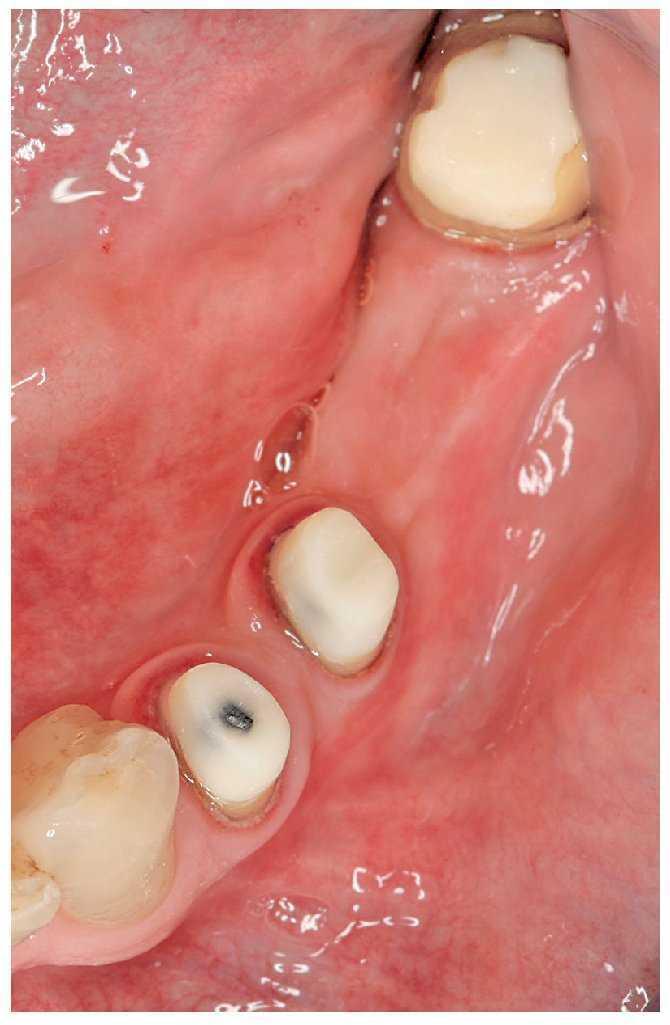

Figura 5a. Ausencia del diente 36, dientes adyacentes destruidos por caries.

Figura 5b. Reconstrucción de los muñones después de la extrusión ortodóncica mediante imanes de los dientes pilares18.

Figura 5c. Puente de metal cerámica que sustituye al diente 36.